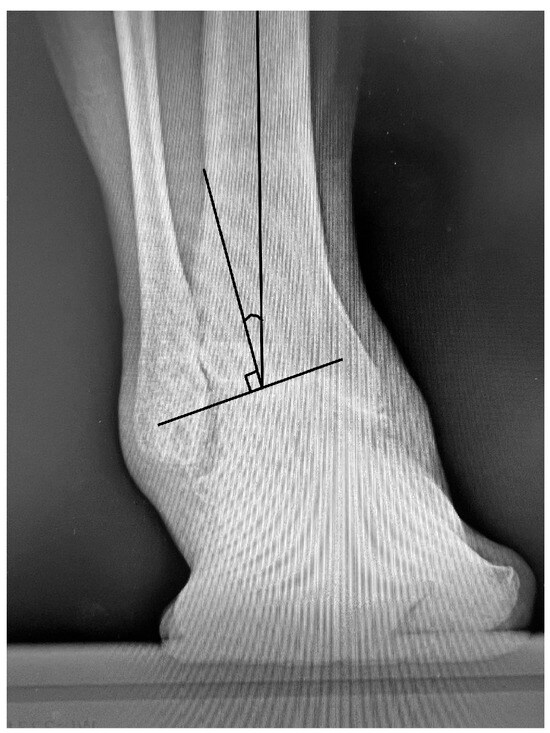

Background: Covering the defects around the calcaneus is still a largely debatable subject. In the classical view, the defects at the level of the foot can be treated only by a free flap. In a modern approach, it has been observed that for small or m...